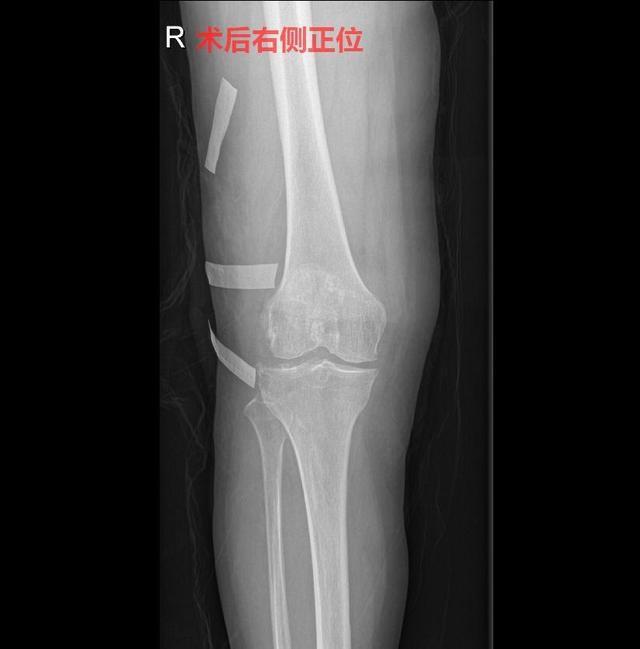

完善检查后,与家属沟通,随后进行手术治疗,在腰麻下行右膝关节镜检治疗术+切开清理术,术中见右膝关节内滑膜增生,关节内多发软骨性、骨性游离体,各骨关节软骨磨损剥脱,骨赘形成。予清理滑膜,取出游离体,切开探查并清理股骨内外侧骨赘,术后予止痛、止吐、护胃、补液等对症治疗。